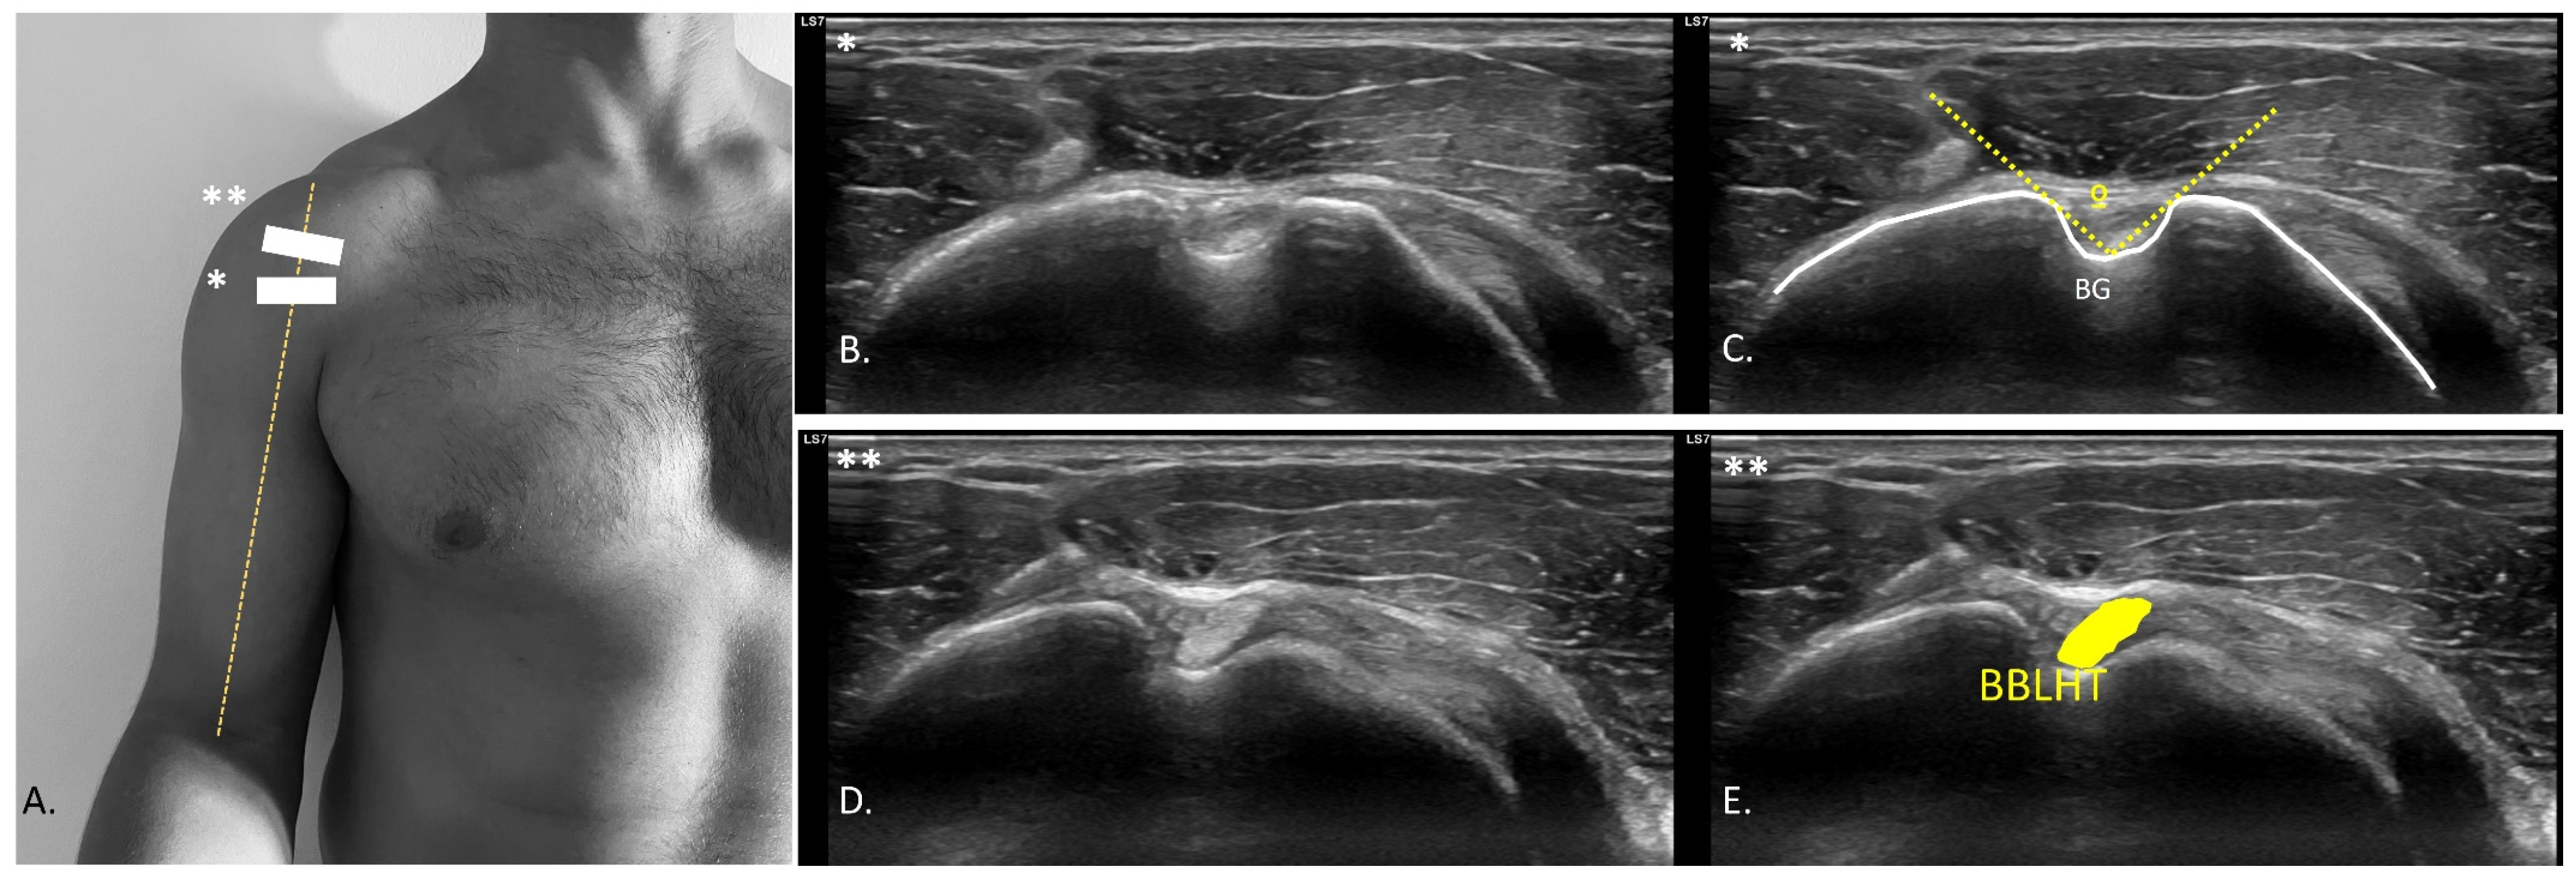

2.5. USI Assessment

- Mazaleyrat, M.; Barthélémy, R.; Bouilleau, L.; Charousset, C.; Berhouet, J. Inter- and intra-observer reproducibility of ultrasound analysis of the long head of the biceps. Orthop. Traumatol. Surg. Res. 2020, 106, 235–239. [Google Scholar] [CrossRef] [PubMed]

- Cardoso, A.; Freire, G.; Alonso, R.; Afonso, P.D.; Pires, L. Bicipital groove cross-sectional area on ultrasonography: Does a correlation to intra-articular tendon pathology exist? Orthop. Traumatol. Surg. Res. 2021, 107, 102747. Available online: https://pubmed.ncbi.nlm.nih.gov/33333282/ (accessed on 16 July 2025). [CrossRef] [PubMed]

| BBLHT CSA (cm2) | 0.11 ± 0.02 (0.08–0.16) | 0.12 ± 0.02 (0.08–0.16) | −0.01 (−0.2–0.01) | 0.177 (0.31) |

| BG (°) | 118.26 ± 8.17 (95.00–130.80) | 117.55 ± 10.66 (95.40–132.00) | 0.71 (−3.31–4.74) | 0.714 (0.08) |